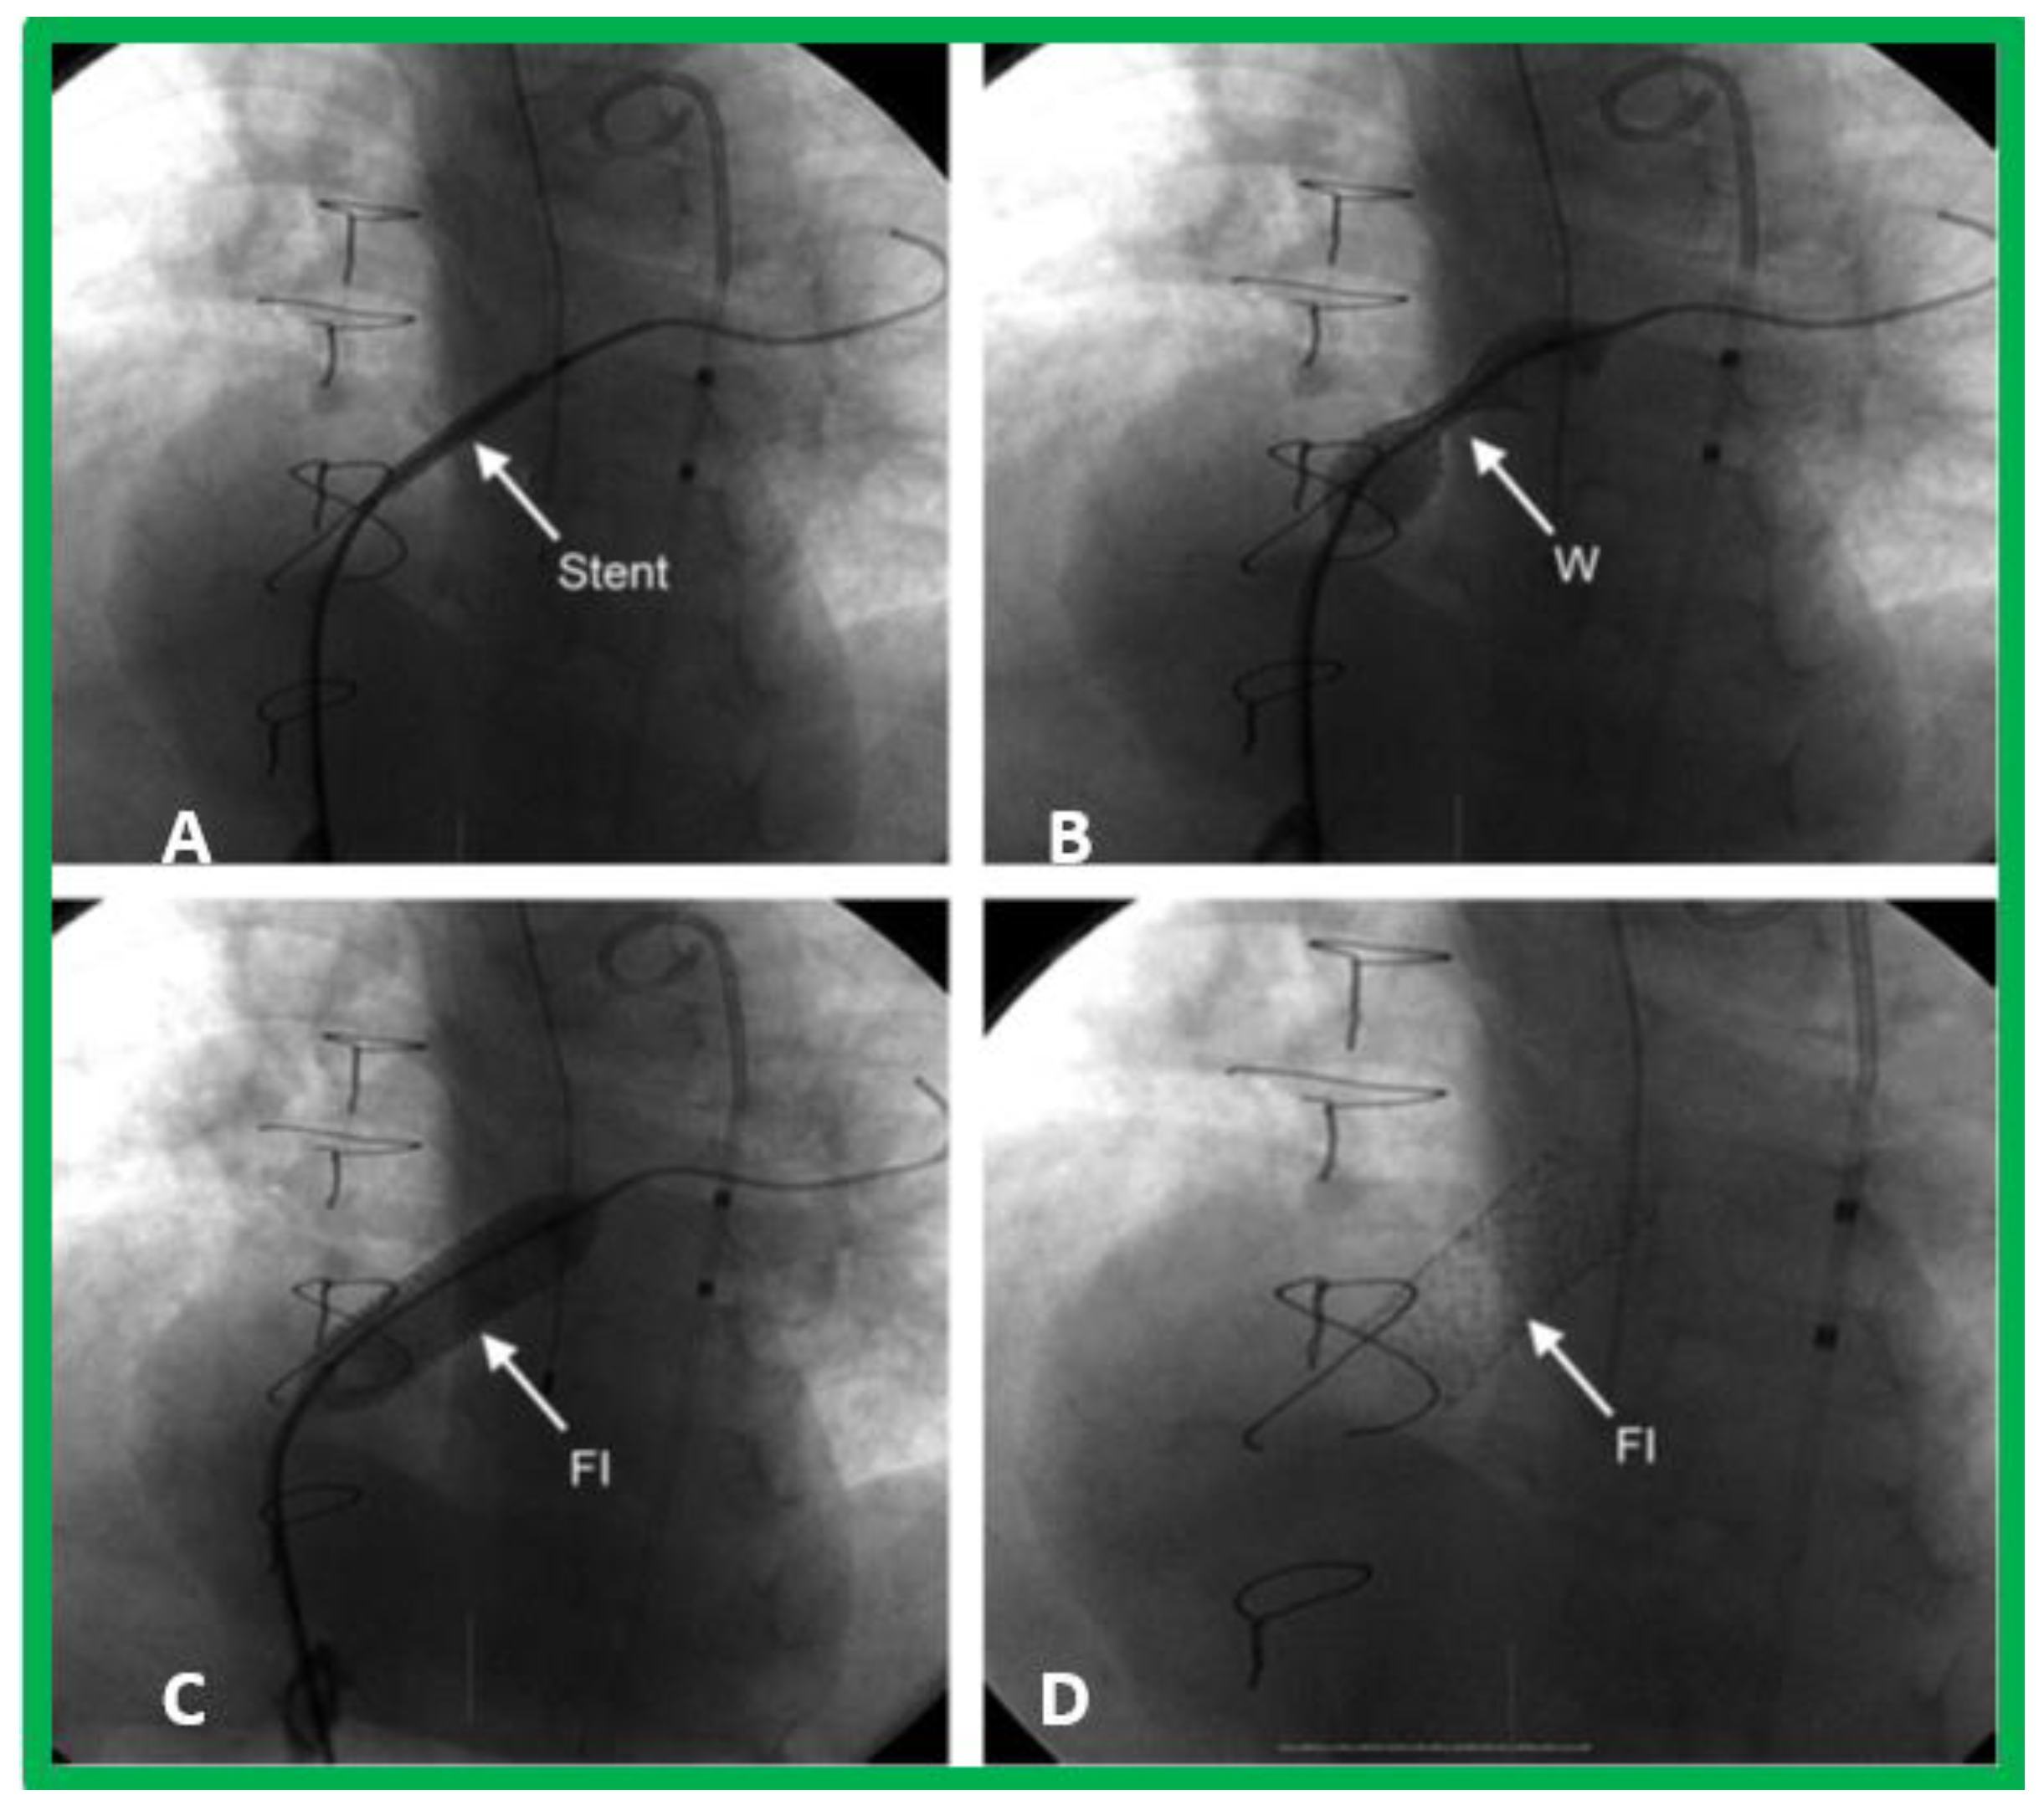

10.1.1. Inter-Atrial Obstruction